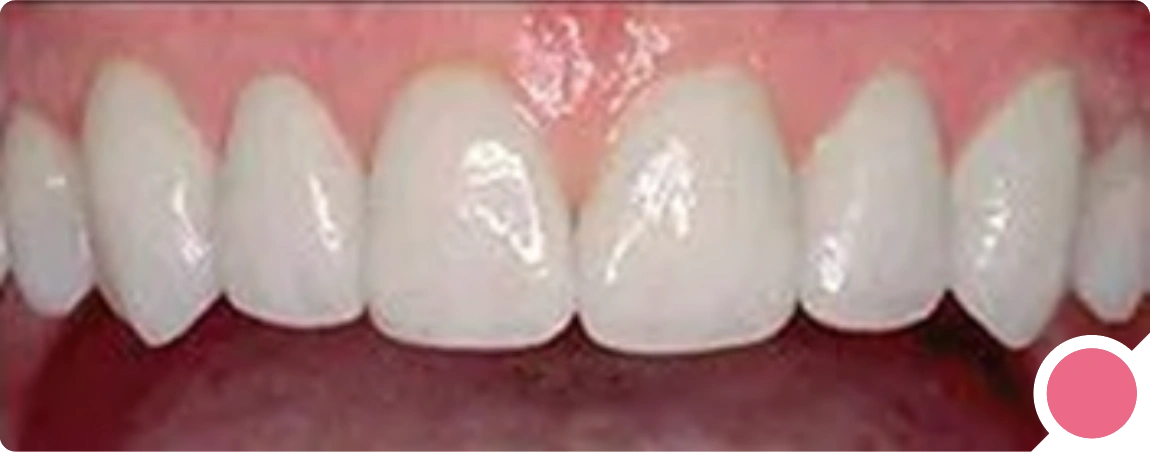

Photograph Requirements

Photograph Requirements